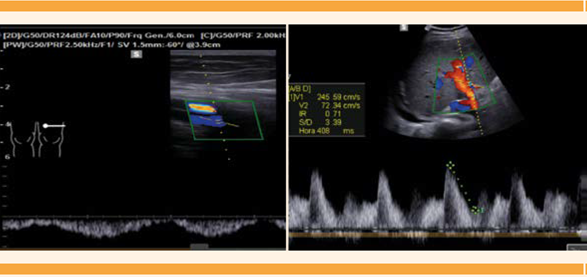

El Doppler de los miembros pélvicos reportó datos de estasis venosa bilateral, negativo para trombosis. El ultrasonido hepático documentó incremento de la perfusión hepática arteriovenosa, quizá secundaria a sobrecarga hídrica. Figura 3

Figura 3 Doppler de miembro pélvico (izquierda). Ultrasonido hepático con incremento de la perfusión hepática arteriovenosa (derecha).